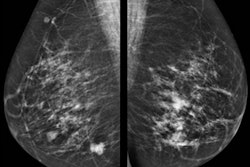

Hologic and Bayer are entering into a partnership to deliver contrast-enhanced mammography (CEM) to improve breast cancer detection for women across Europe, Canada, and the Asia Pacific region.

The deal brings together Hologic's mammography gantries and Bayer's CEM-approved injection systems to allow for contrast media administration during a mammography exam. With the new agreement, the companies aim to support radiologists and the needs of their teams by providing a comprehensive product package and hands-on training.

Through this agreement, the companies say they will help increase access to additional breast imaging technology that may also improve health outcomes for patients. They also noted increased interest in CEM over the past few years for diagnostic breast imaging.